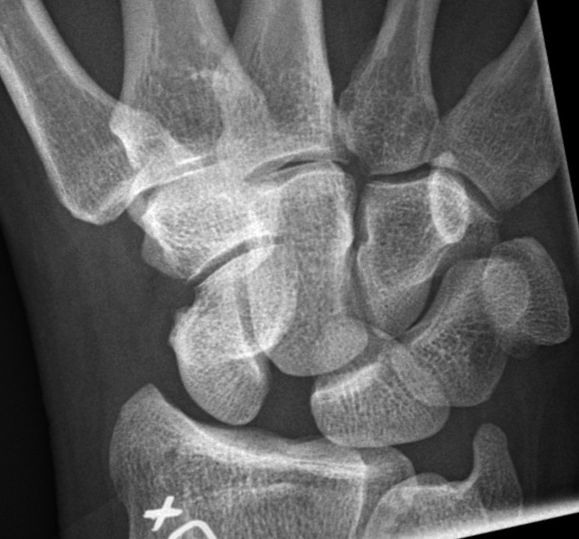

- Ökat avstånd mellan skafoideum och lunatum på frontalbild av handled. Ska normalt vara < 3 mm, > 5 mm är patologiskt. Men detta visas på röntgen först 3-4 månader efter skada. [2]

- Man kan göra slätröntgen med provokation - med knuten hand och handleden i neutralläge, radial- resp. ulnardevierad. Detta kan visa dynamisk instabilitet med ökat avstånd mellan skafoideum och lunatum vilket föregår statisk instabilitet, men syns ändå inte förrän efter ett par månader.

Ökat avstånd mellan skafoideum och lunatum vid ulnardeviation